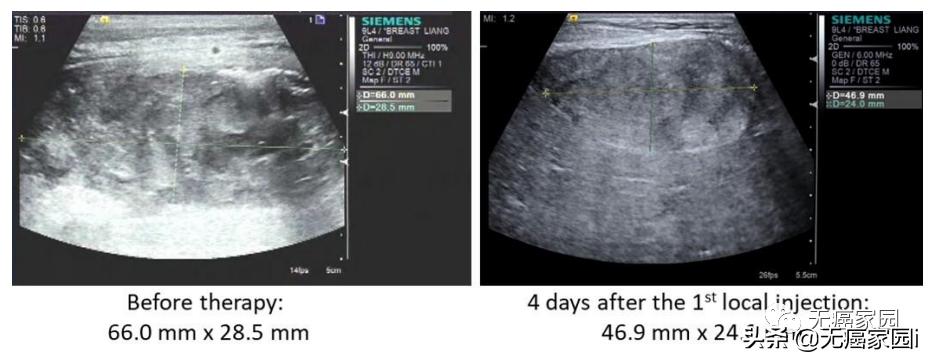

本研究中,采用局部输注 NKG2Dp CAR-NK的方式治疗了3 例转移性结直肠癌患者。前两例患者腹腔输注低剂量 CAR-NK 细胞后,可观察看 腹水生成量减慢以及腹水样本中肿瘤细胞的数量急剧减少 。 第三例肝转移瘤患者 采用超声引导下瘤内经皮注射和腹腔内灌注方式输注 CAR-NK细胞后, 多普勒超声可见肝部肿瘤快速缩小 ,正电子发射断层扫描 (PET-CT)提示经治疗的肝病灶为完全代谢反应。 3 例患者在治疗过程中均无出现3级或以上的不良事件。

第3例患者多普勒超声成像显示局部注射 CAR-NK 细胞降低肝转移病灶肿瘤负荷